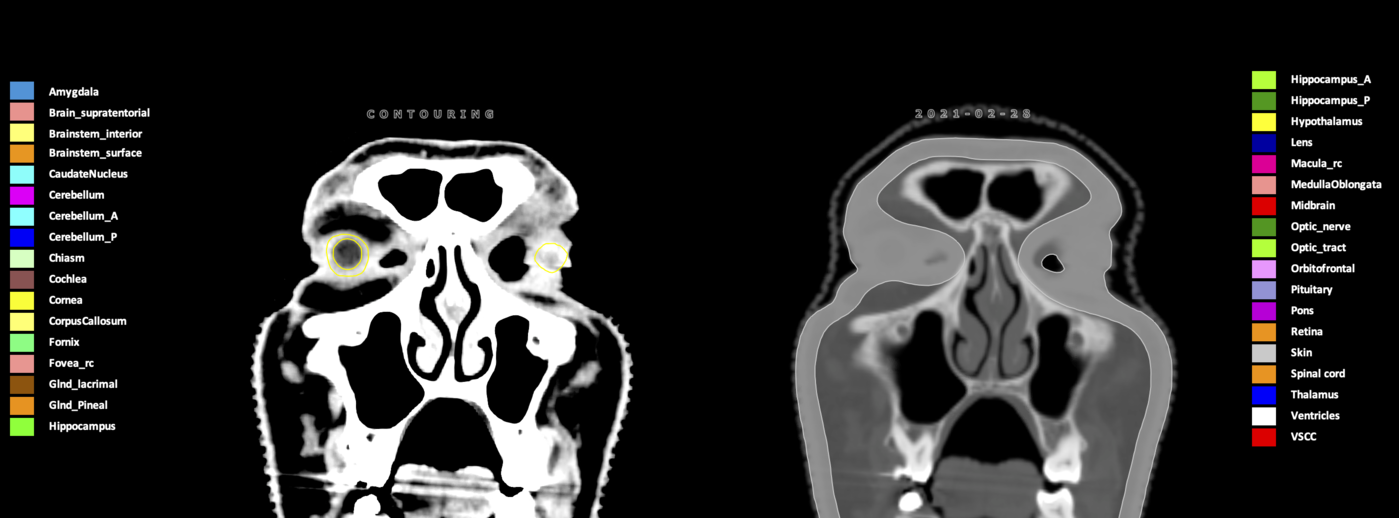

Eekers et al. have published an international neurological atlas for contouring of organs at risk in consensus with the European Particle Therapy Network (EPTN) in 2018 and an update in 2021. The purpose of this consensus atlas is to decrease inter- and intra-observer variability in delineating OARs relevant for neuro-oncology.

Included are all OARs known to be relevant for radiation-induced toxicity in neuro-oncology: brain, brainstem (midbrain, pons, medulla oblongata), chiasm, cerebellum (anterior & posterior), cochlea, cornea, hippocampus (anterior & posterior), hypothalamus, lens, lacrimal gland, optic nerve, pituitary, skin, and vestibular & semicircular canals. To further facilitate research on cognition, vision and radiological changes after irradiation of the brain, potential clinically-relevant OARs are included: amygdala, caudate nucleus, cerebellum (anterior & posterior), corpus callosum, fornix, macula, optic tract, orbitofrontal cortex, periventricular space (PVS), pineal gland, and thalamus.

Three-dimensional delineation of the 25 consensus OARs for neuro-oncology are shown on CT (WW/WL 120/40, 3000/600), 3T MR images, (T1Gd, T2FLAIR 1mm) and 7T MR (MP2RAGE 0.7 mm). All are presented in transversal, sagittal and coronal view.